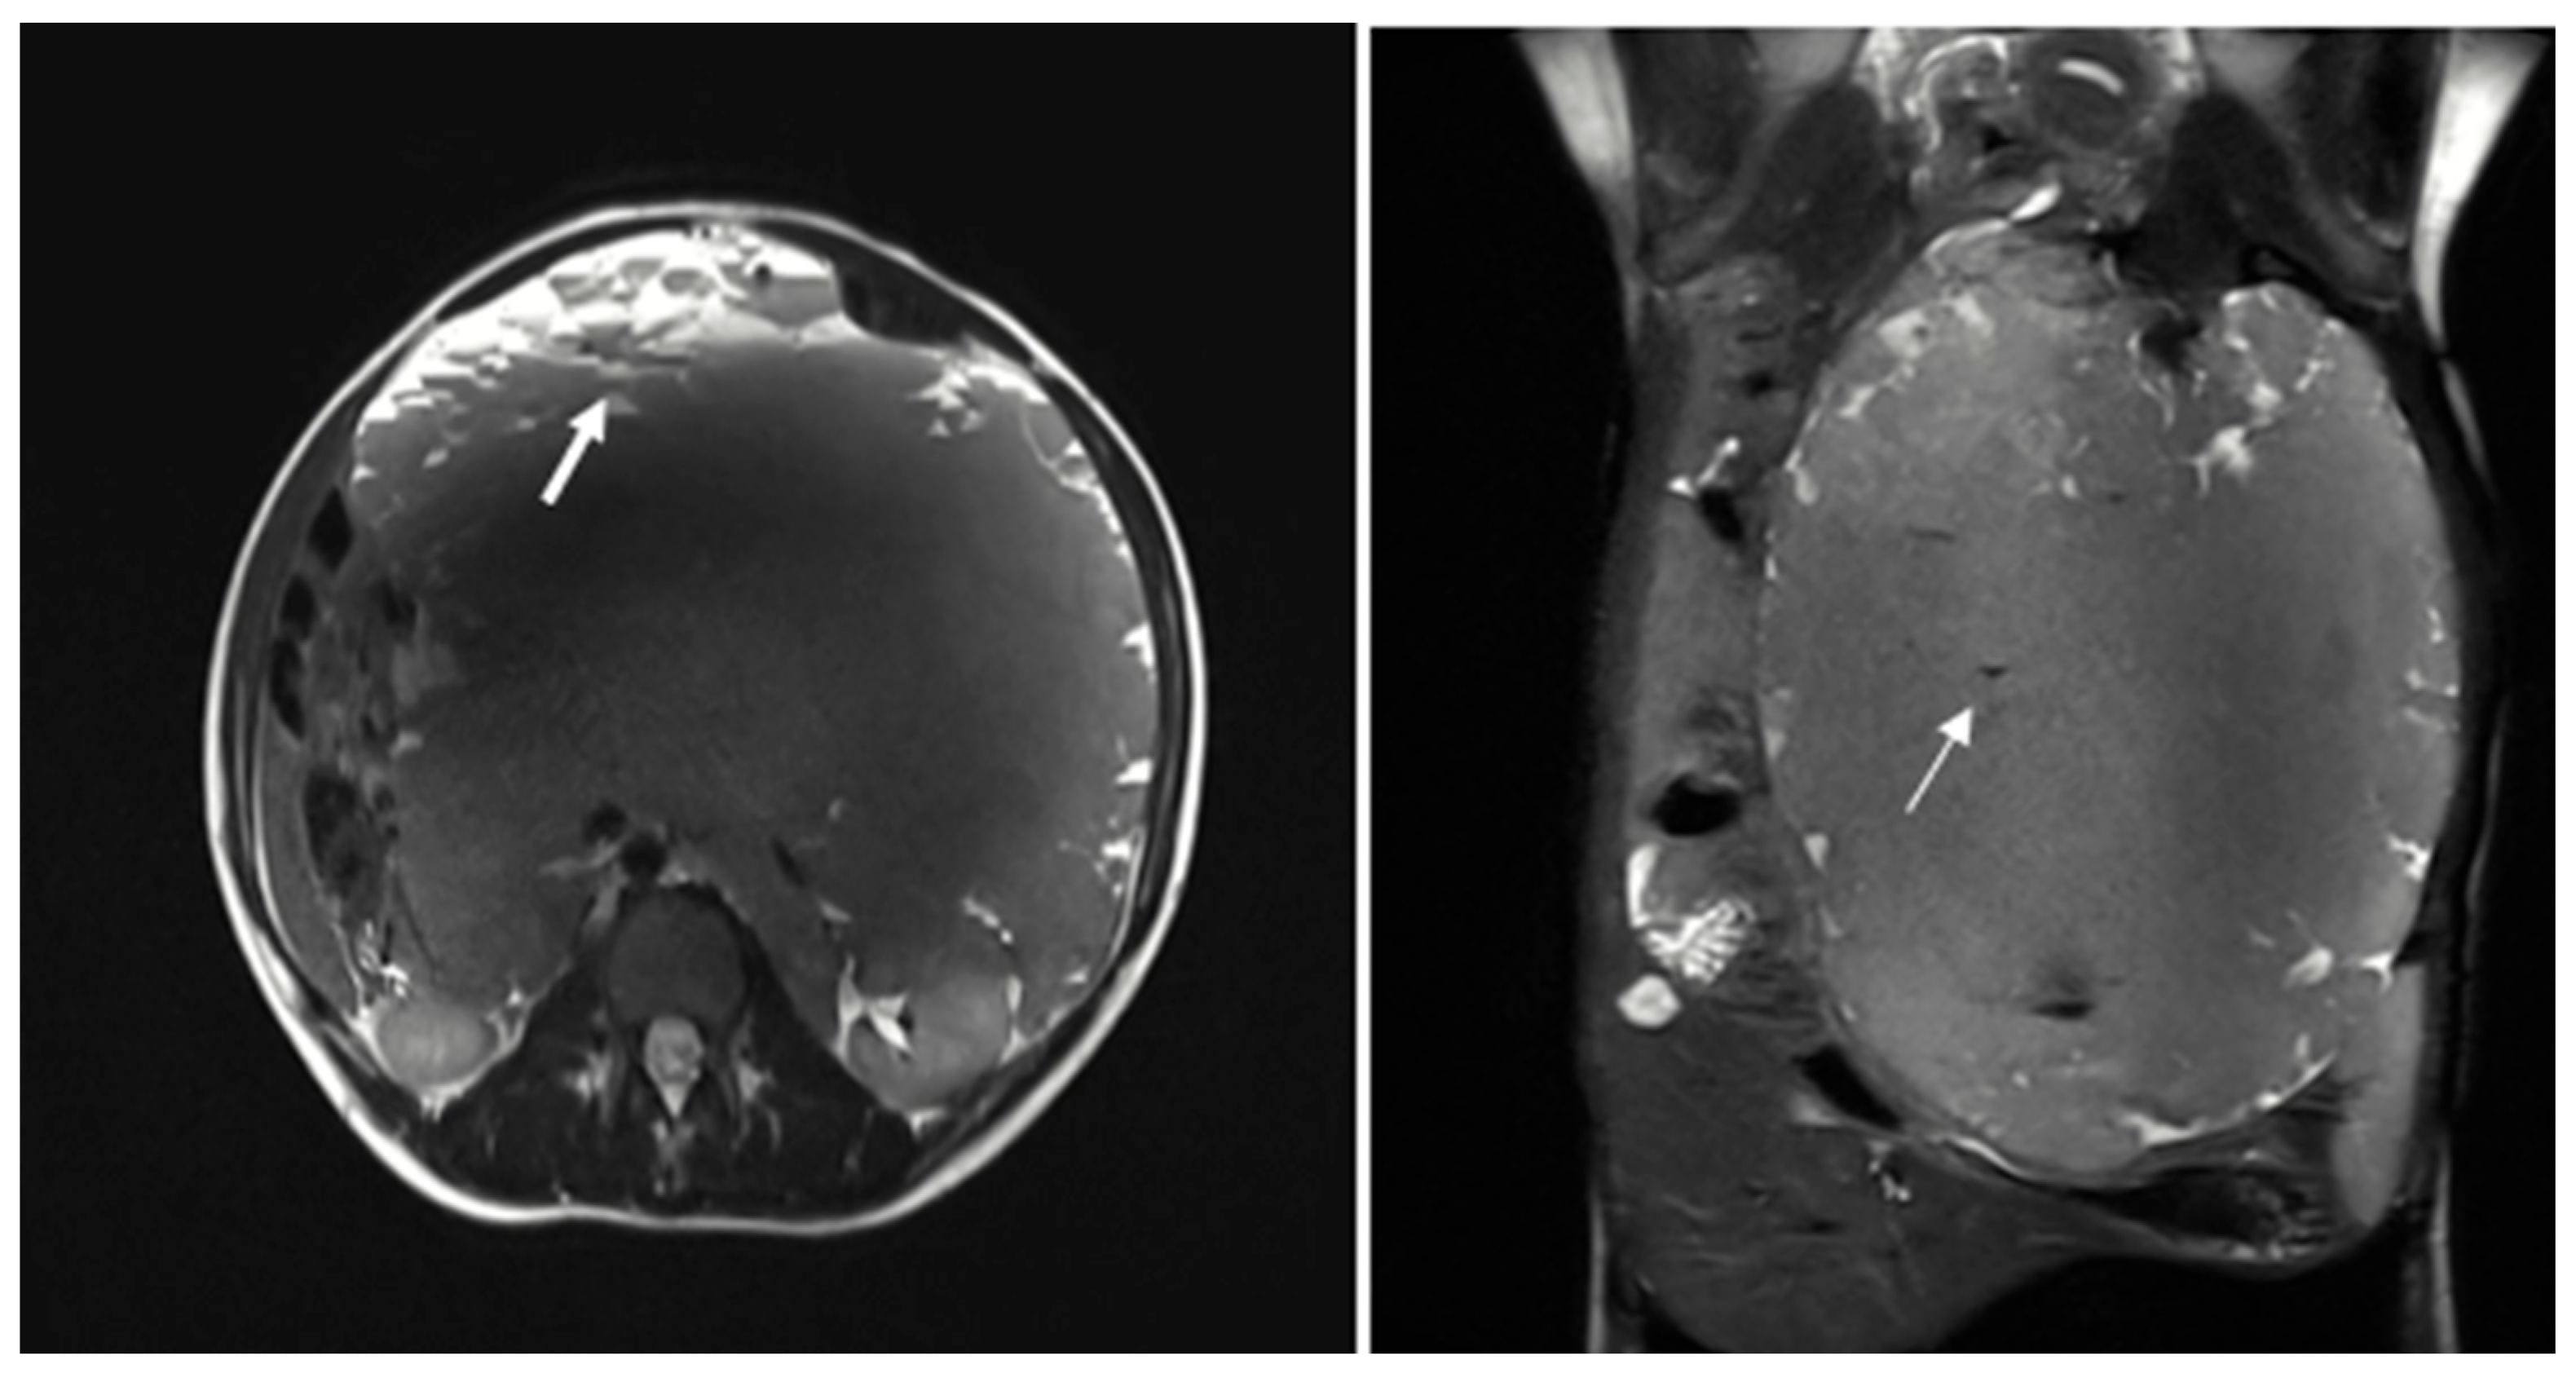

The patient was subsequently admitted for further evaluation, and an abdominal MRI was performed. Imaging sequences included T2-weighted sequences and T1-weighted sequences, with and without fat suppression. However, due to limited patient compliance, the study was interrupted before the contrast agent administration. Despite these limitations, MRI confirmed the presence of a large multiloculated mass with peripheral cystic components exhibiting fluid-debris levels (Figure 2).

On MRI, these malformations are usually well-defined, lobulated, and septated. They predominantly show low signal intensity on T1-weighted images and high signal intensity on T2-weighted images. The signal intensity can vary depending on the amount of protein or hemorrhage in the lesion. Occasionally, the content may appear brighter than muscle on T1-weighted images, particularly in cases where the cyst contains protein or blood. Generally, the enhancement after contrast medium agent administration is visible only in the septa and solid components. However, if there is inflammation, the septa surrounding areas may also show significant enhancement [6].

Figure 2. The multiloculated mass shows variable signal intensity on T2 sequences and presents cystic formations peripherally, exhibiting fluid-debris levels (thick arrow). Some calcified spots with low T2WI signals were also noted within the mass (thin arrow).